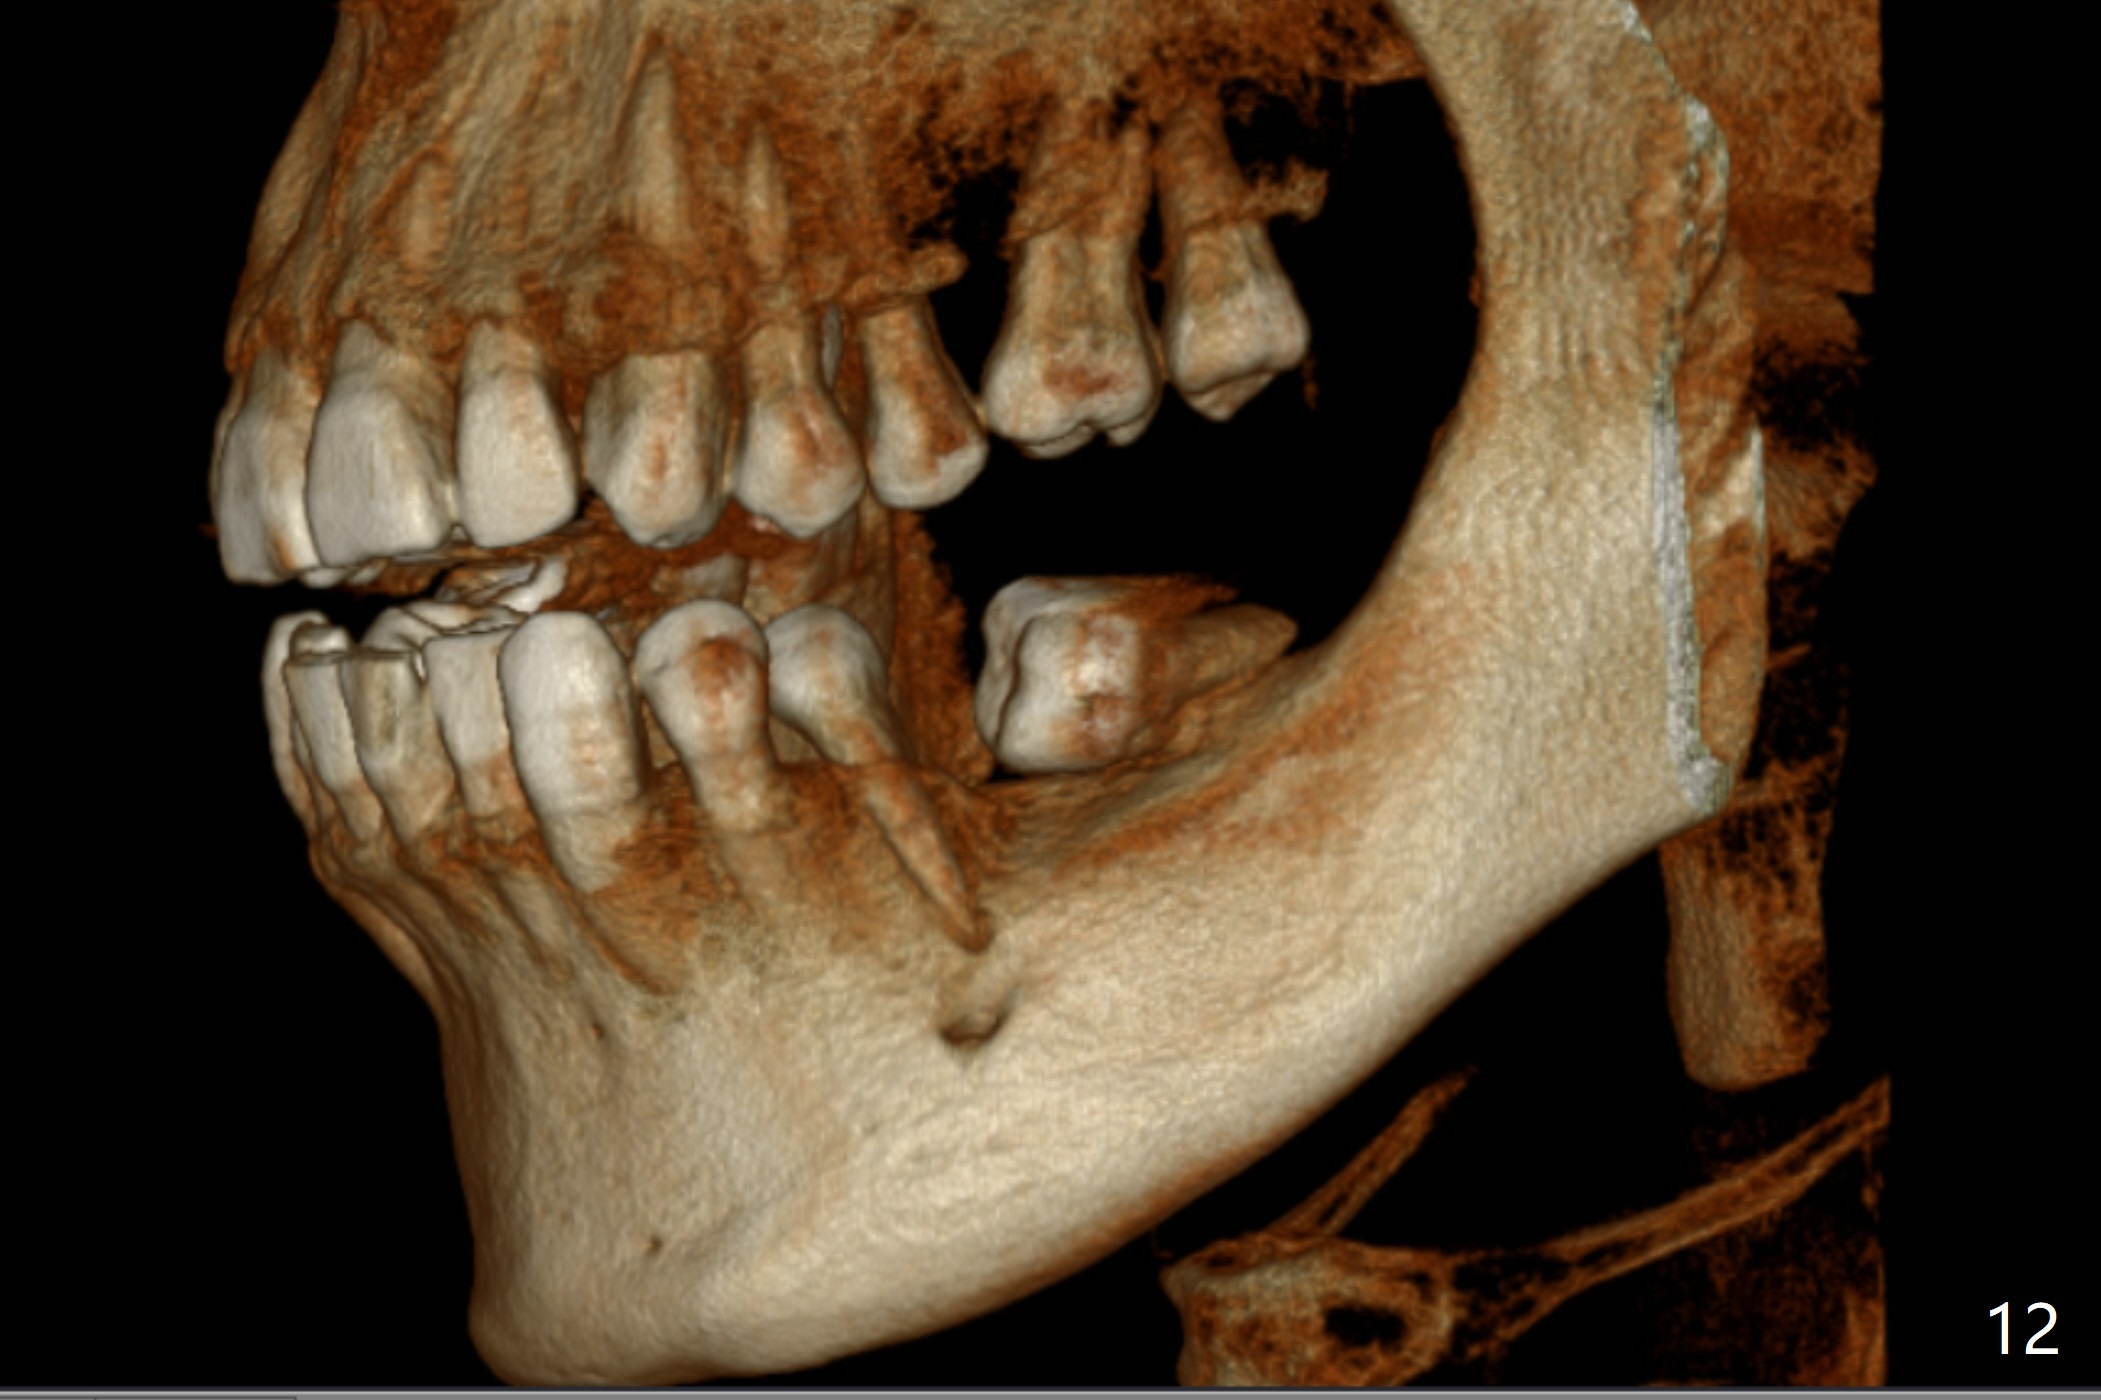

A 43-year-old man has poor dentition on the left: 1st molar missing, 2nd molar mesial inclination (Fig.1) and 2nd bicuspid lingual tilt (Fig.2). The latter is nonfunctional (Fig.3 (linguoposterior view). Two molar implants will be placed in a position so that their crowns will be in cross bite (Fig.4,5), the same occlusal scheme as the teeth #21 and 22. When these implants osteointegrate, the provisional crowns (Fig.6 P) will be supraocclusal so that there is clearance (*) for #20 to upright orthodontically (Fig.7-9). Moreover, these implants will be used anchorage as well as #21 and 22. Panoramic X-ray (Fig.1) and CBCT (Fig.10-12) show limited bone height at the sites of #18 and 19. It appears that 5x8 and 5.9x6 mm implants are appropriate with ridge reduction at #19.